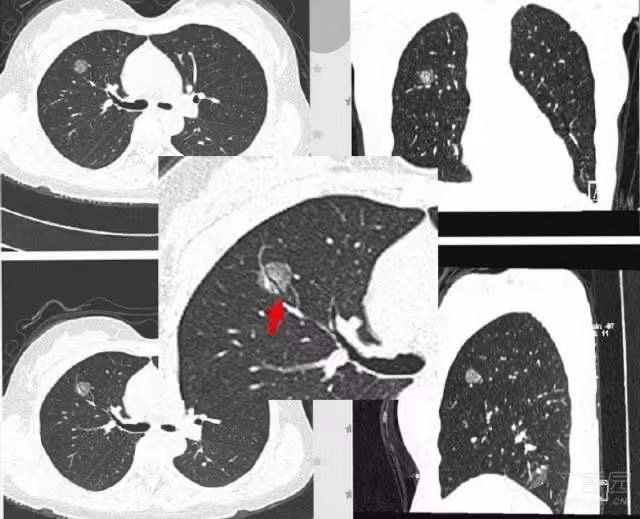

周围型肺癌:病灶最大径>30 mm,右肺上叶后段可见一肿块,边缘分叶。

肺脓肿:右下肺可见一厚壁空洞,内可见液平,外缘模糊。

5. 1.2 癌性空洞:空洞壁厚薄不均,近肺门侧较厚,且可见壁结节凸向腔内。